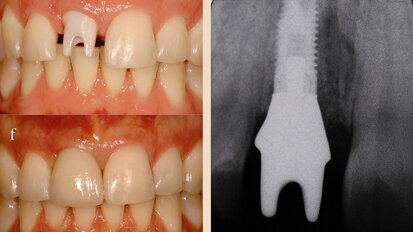

Neoss photos

Neoss Implantat System